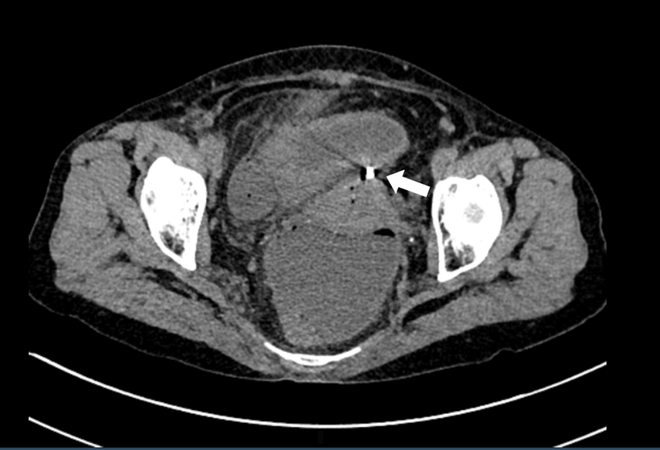

Một bệnh nhân bị thủng tử cung do đặt dụng cụ tránh thai 30 năm ảnh 2Lỗ thủng đáy tử cung (mũi tên trắng ở hình A_ và dụng cụ tử cung (mũi tên ở hình B). (Ảnh: BVCC)

Bệnh nhân vào viện trong tình trạng viêm phúc mạc toàn thể, khí tự do ổ bụng, thủng ruột non và dụng cụ tránh thai nằm ngoài thành tử cung. Các phẫu thuật viên trực mổ mở cấp cứu cắt tử cung bán phần, khâu lỗ thủng ruột non và rửa sạch ổ bụng cho bệnh nhân.

Kíp bác sỹ phẫu thuật lập tức tiến hành mổ mở cấp cứu cắt tử cung bán phần, khâu lỗ thủng ruột non, rửa sạch ổ bụng. Tuy nhiên, sau mổ 6 ngày, bệnh nhân phải mổ lại lần thứ hai để đưa hai đầu ruột non ra ngoài tạm thời do bục lỗ khâu ruột non. Quá trình hậu phẫu ổn định, người bệnh đã ổn định sức khỏe.